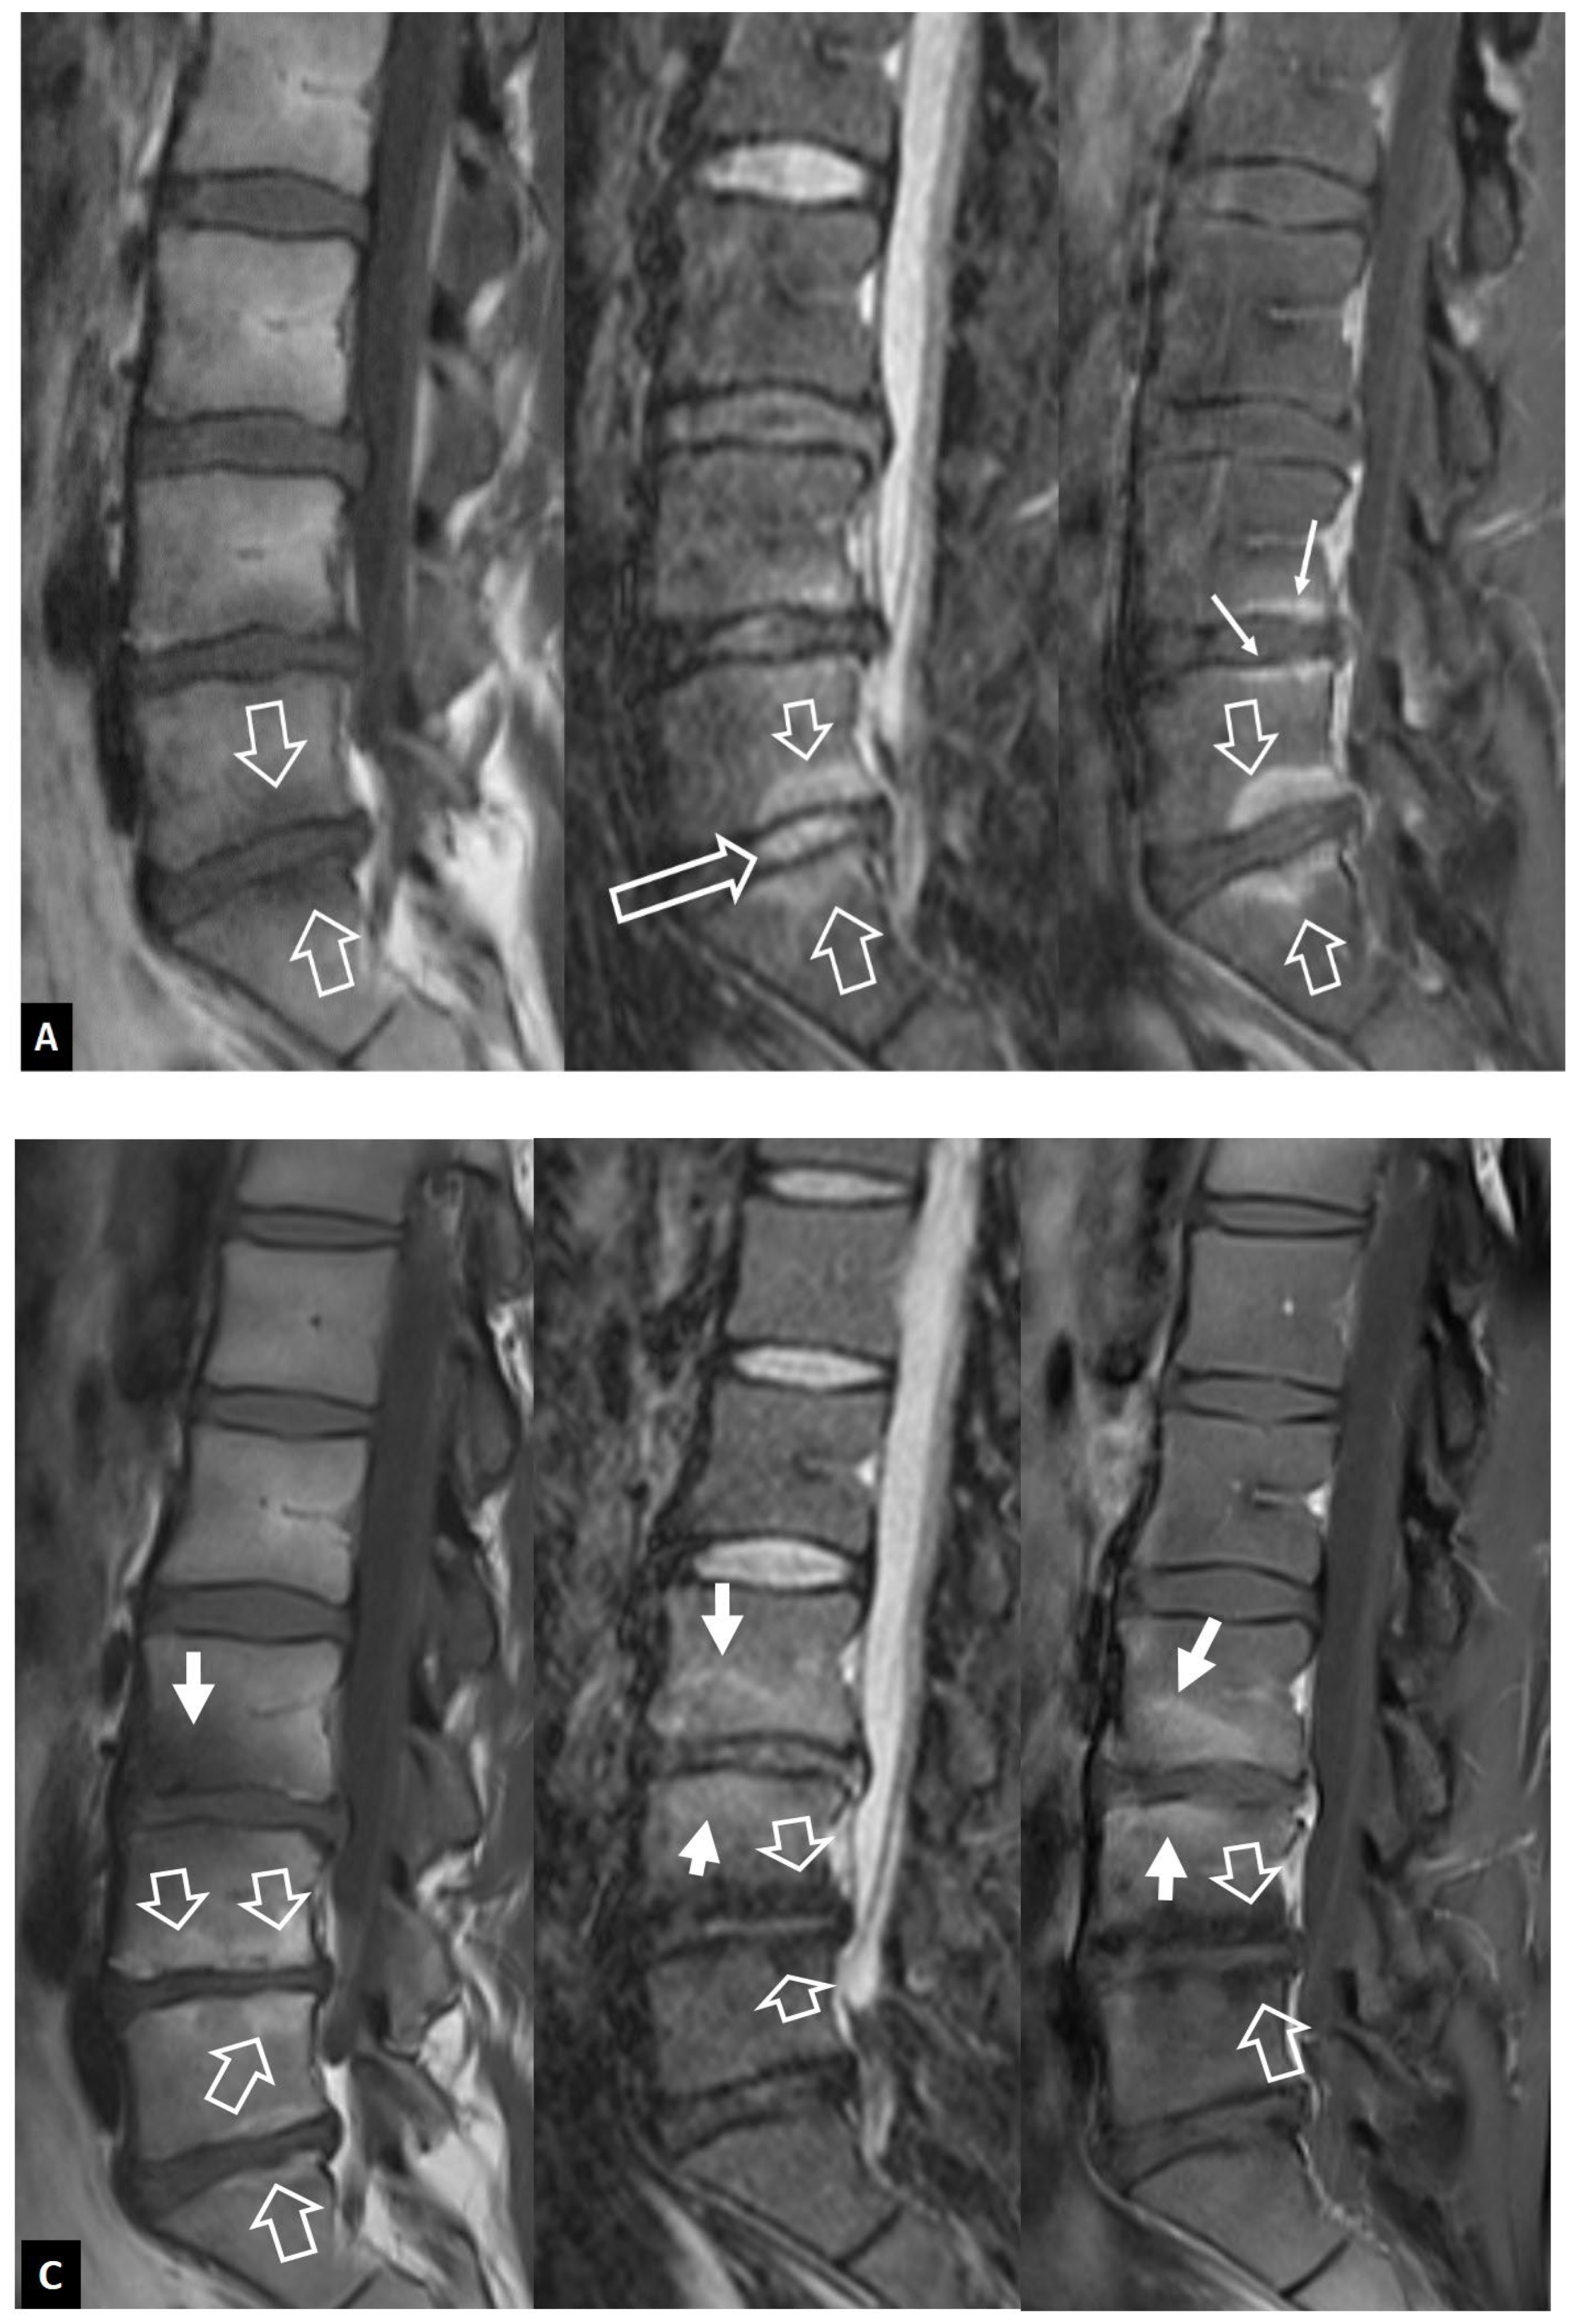

1. a.ii. Aseptic Spondylodiscitis

1. a.iii. SAPHO Syndrome

1. a.iv. Destructive Spondyloarthropathy

1. a.v. Crystal Deposition